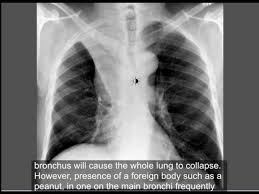

Suctioning the lungs during surgery helps clear them, but sometimes they still build up. Removing obstructions by bronchoscopy 4. Treating a tumor or underlying condition, if present. Using surgery or medicine, doctors can remove the source of the pressure. Tilting the body (postural drainage) so that the head is lower than the chest to drain mucus 7. Treatment depends on the cause and severity of the collapse. Obstructive atelectasis may be caused by many things, including: See full list on mayoclinic.org Atelectasis is treated by the division of pulmonary medicine. The nurses or respiratory therapists may guide you with some breathing exercises. You may develop atelectasis if you breathe in a foreign object. See full list on hopkinsmedicine.org Foreign body.atelectasis is common in children who have inhaled an object, such as a.

If you do have signs and symptoms, they may include: However, some residual scarring or damage may occur. Weak breathing (respiratory) muscles due to muscular dystrophy, spinal cord injury or another neuromuscular condition 8. Mucus plugs are also common in children, people with cystic fibrosis and during severe asthma attacks. Atelectasis, the collapse of part or all of a lung, is caused by a blockage of the air passages (bronchus or bronchioles) or by pressure on the lung. risk factors for atelectasis include anesthesia, prolonged bed rest with few changes in position, shallow breathing and underlying lung disease.